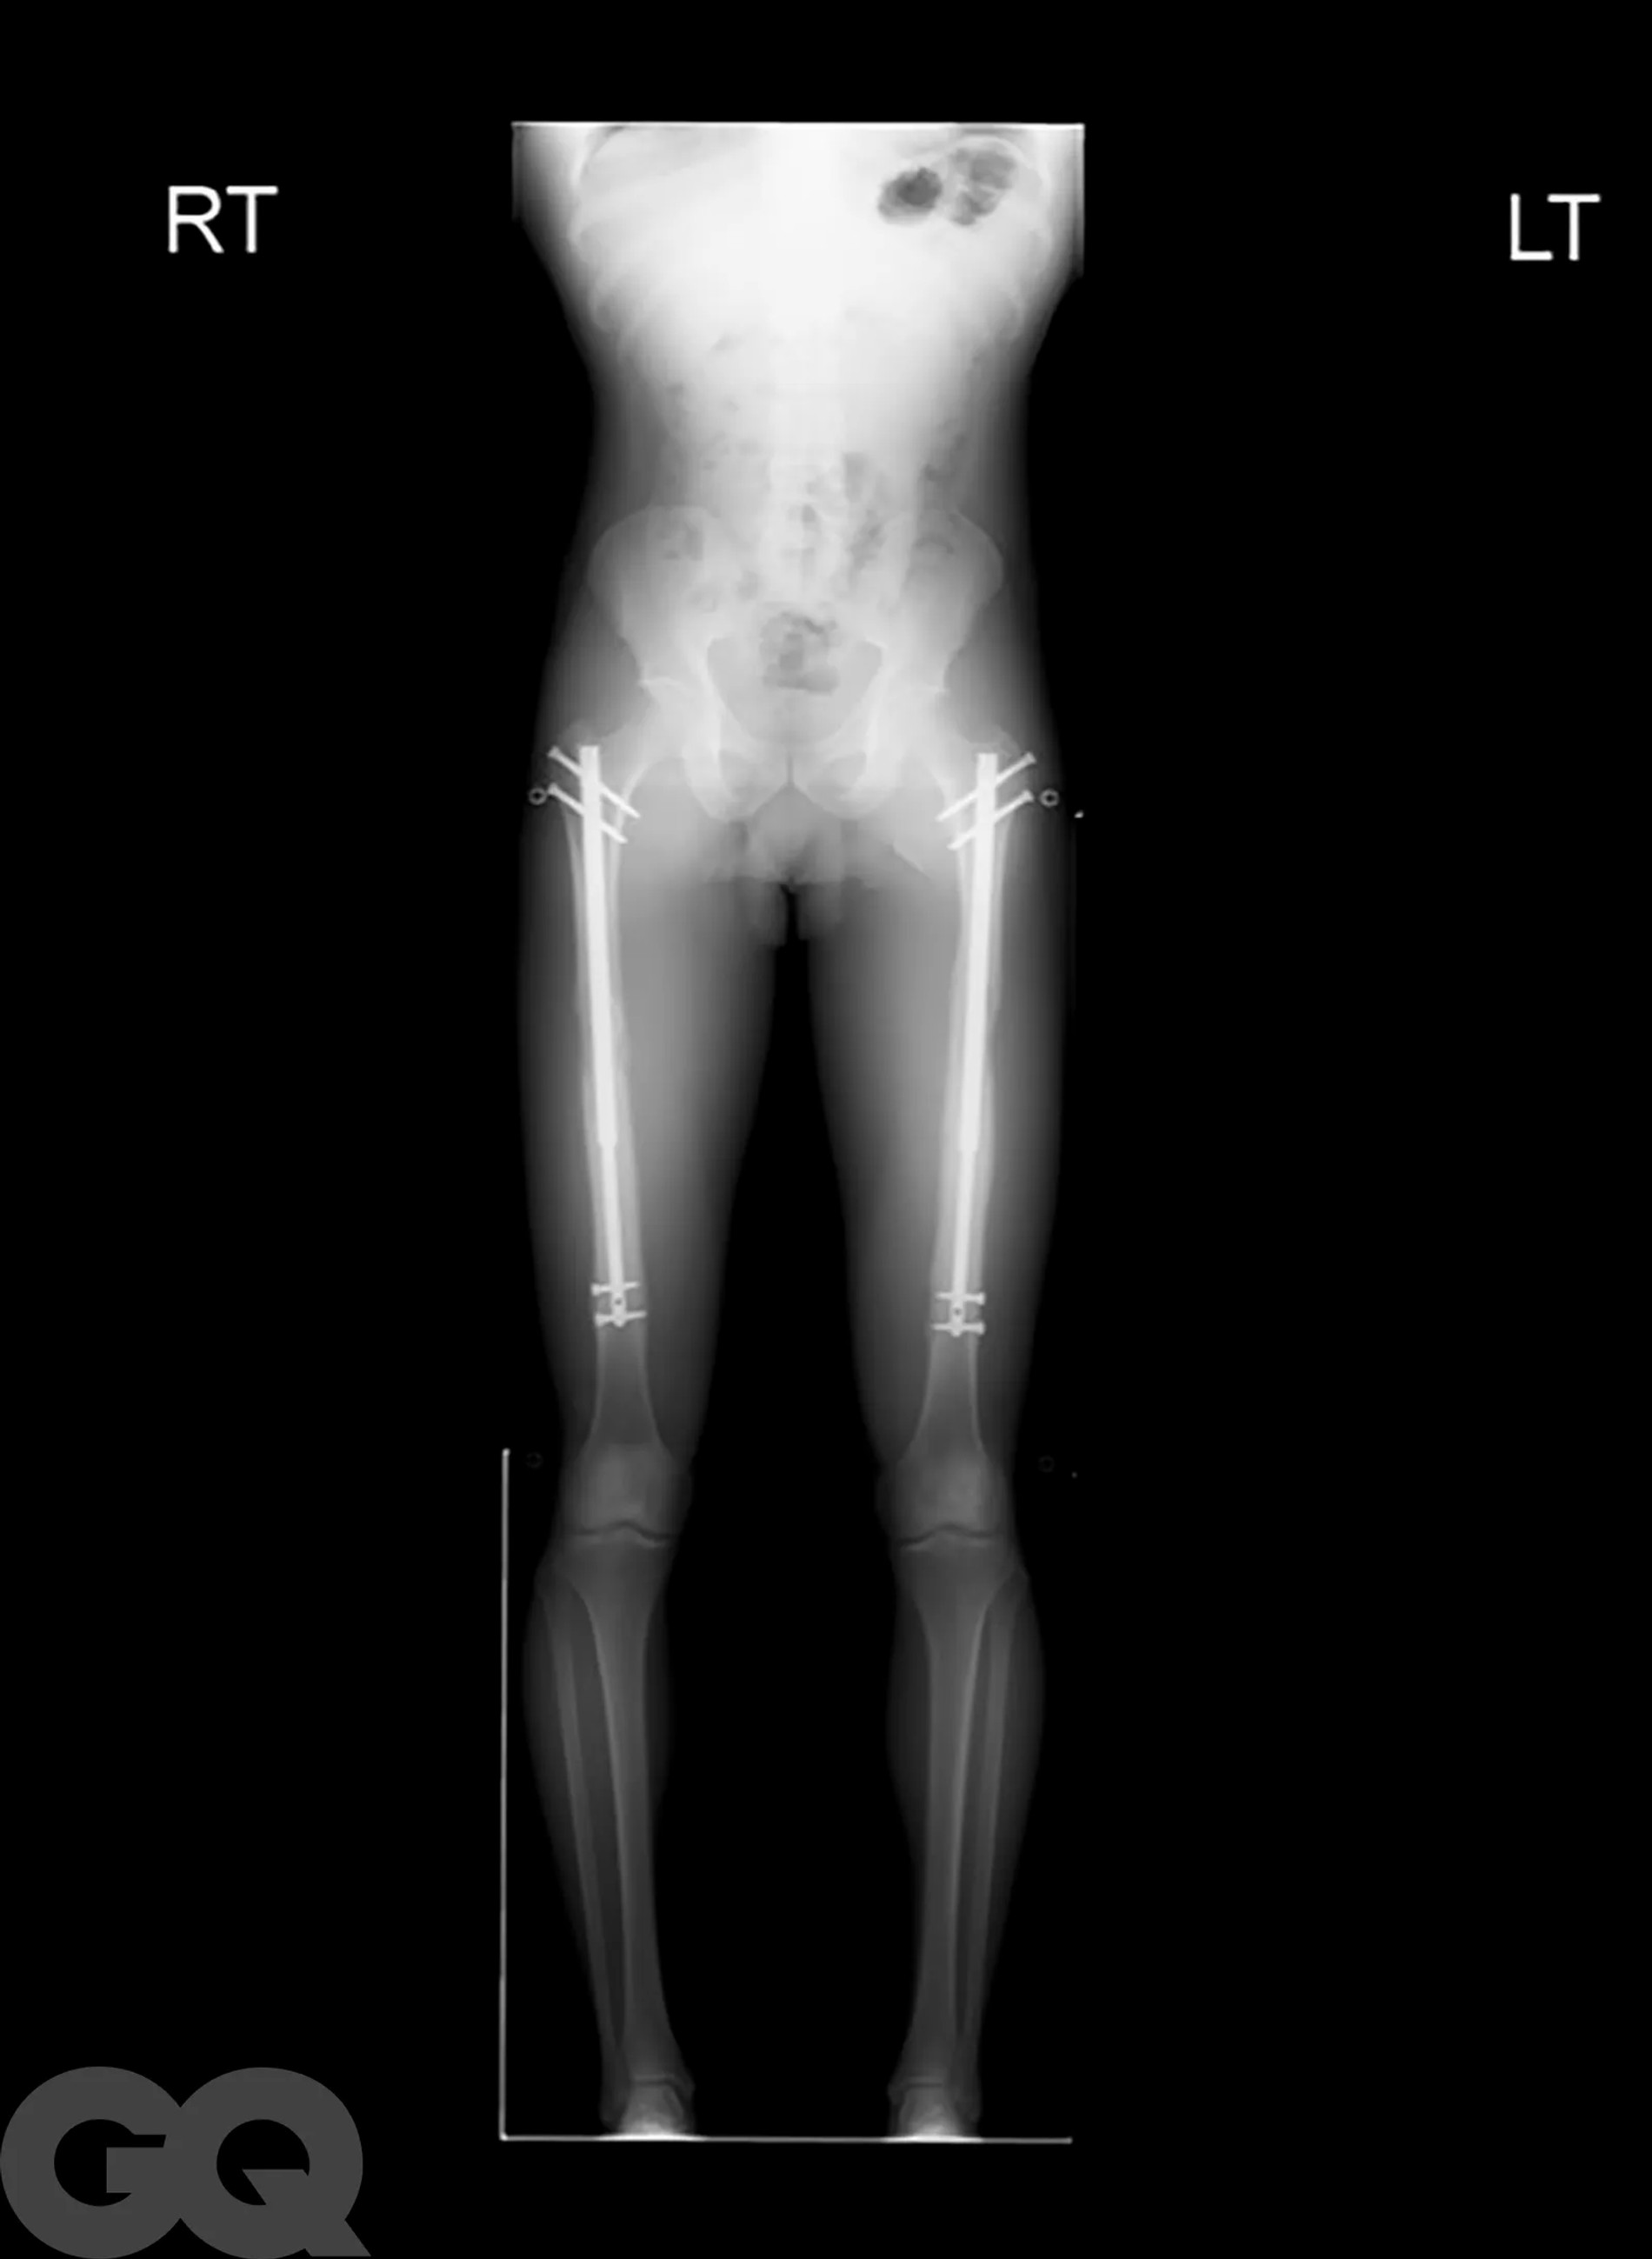

Надо сказать, что операция эта больше напоминает самую настоящую экзекуцию. Она основана на методике советского хирурга-ортопеда Гавриила Илизарова, которая изначально была разработана для пациентов со сложными переломами костей. Американские специалисты ее доработали и сделали более щадящей, но все же. В погоне за несколькими добавочными сантиметрами мужчины соглашаются на то, чтобы их собственные бедренные кости были сломаны. Да, без этого никак.

После перелома между костями вставляют регулируемые титановые стержни, которые наращивают на один миллиметр каждый день в течение примерно 90 суток с помощью магнитного пульта дистанционного управления. Как только сломанные кости срастутся, человек становится выше ростом и снова может ходить. Обычно весь процесс занимает 1 год, реабилитация сопровождается болью, что нисколько не смущает мужчин, решивших немного подрасти.

Не останавливает их и тот факт, что удовольствие это, прямо скажем, из дорогих: мужчины раскошеливаются на суммы от 70 до 150 тысяч долларов, в зависимости от того, сколько дюймов они хотят нарастить. И даже берут на подобные цели кредиты! Большинство выбирают стандартные три дюйма — это при условии, что экзекуции подвергнутся только бедра. Если и этого недостаточно и хочется еще немножко подрасти, спустя время врачи предлагают таким же образом переделать и голени.